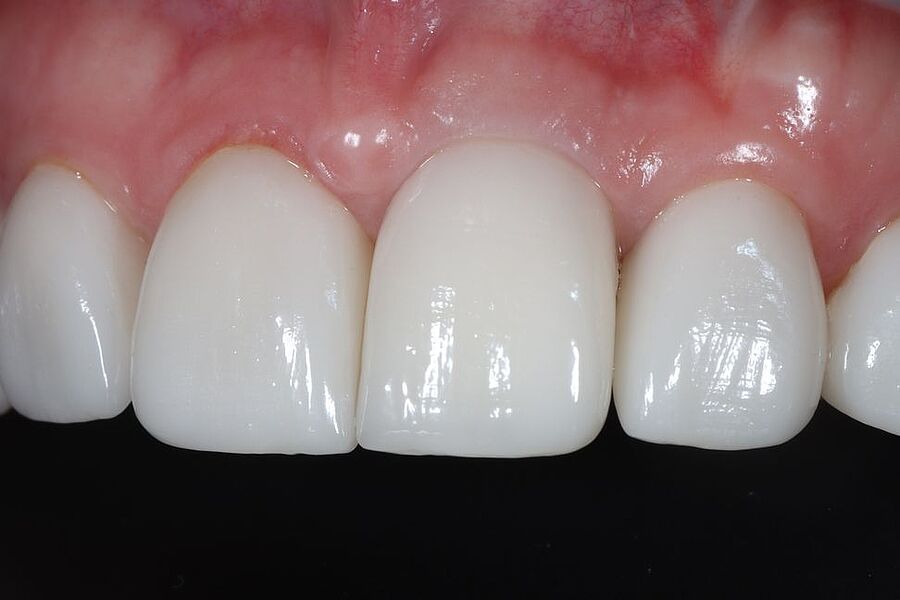

Im Journal Zahnmedizin up2date demonstrieren unsere Ästhetik-Spezialisten in einem weiteren Beitrag zum Thema professionelle Zahnaufhellung wie ein entsprechend angeleitetes At-Home-Bleaching funktioniert. Die entscheidende Vorbereitungsphase mit der Herstellung der Schienen und der adäquaten Instruktion des Patienten werden in dieser Publikation anhand eines Bildessays illustriert.

In der Ausgabe 02/2023 der Fachzeitschrift Zahnmedizin up2date berichten unsere beiden Ästhetik-Spezialisten wie ein professionelles In-Office-Bleaching vitaler Zähne funktionieren kann. Die hierzu nötigen Arbeitsschritte einschließlich der klinischen Voraussetzungen werden Schritt für Schritt anhand eines Bildessays illustriert.

Was ist vertretbar, was nicht? Diesen Fragen gehen die drei Autoren dieses im Quintessenz Team-Journal publizierten Fachbeitrags nach. Den Hintergrund bildet, dass aktuell vermehrt Patientinnen und Patienten nach einer Zahnaufhellung nachfragen. Ein strahlend weißes Lächeln steht offensichtlich nicht nur für Gesundheit und Schönheit, sondern wird auch mit Erfolg verbunden. Dabei haben an dem derzeitigen Wunsch nach helleren Zähnen sicherlich die während der Coronapandemie häufig stattfindenden Videokonferenzen ihren Anteil, bei denen – sofern natürlich die Videokamera eingeschaltet ist – das Erscheinungsbild des Gesichts noch mehr in den Vordergrund rückt. Die Autoren zeigen anhand Bilderserien die Anwendungsmöglichkeiten der professionellen Zahnaufhellung, geben Hinweise zu Grenzbereichen und ziehen Grenzen. Klar ist: Richtig angewandt, ist die professionelle Zahnaufhellung ein sicheres und effektives Verfahren.